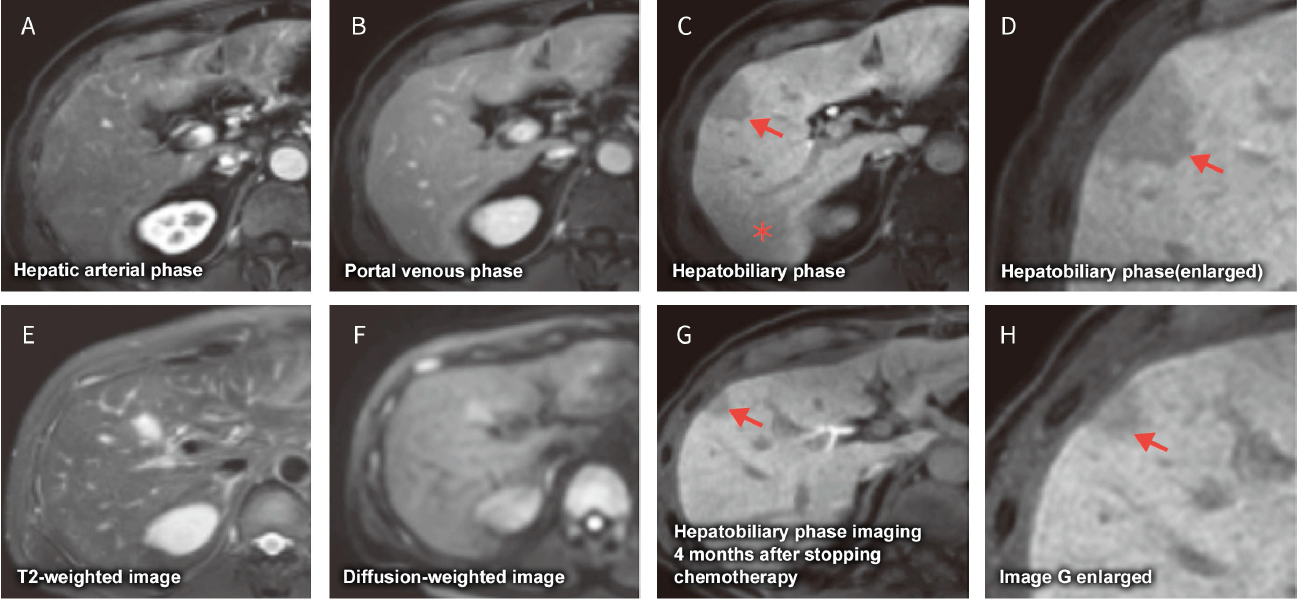

Fig. 25 Male in his 50s receiving chemotherapy (SOX) for gastric cancer

Hepatobiliary phase image (C) reveals heterogeneous and reduced uptake of EOB/Primovist in the entire liver and a faint and ill-demarcated hypointense area (). Hepatobiliary phase images (C, D) reveal a nodule-shaped hypointense area in segment 5 of the liver () not seen on other images. Hepatobiliary phase image (G) obtained four weeks after finishing chemotherapy reveals some improvement of EOB/Primovist uptake in the liver parenchyma and shrinkage of the nodular-shaped hypointense area in segment 5. There is also a faintly punctate region of EOB/Primovist uptake within the nodular-shaped hypointense area.